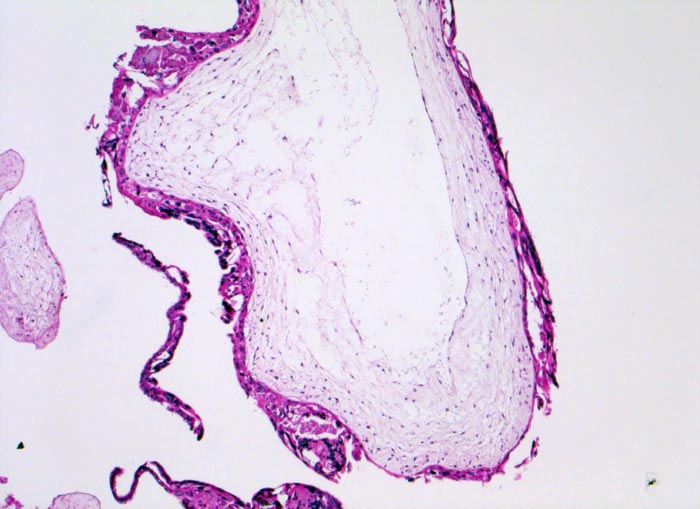

Blasenmole

angeboren /genetisch/Missbildung

Abortmaterial

Paidopathologie

Blasig aufgetriebene Plazentarzotte mit zentraler pseudozystischer Hohlraumbildung (=

Zysterne) und zirkulär proliferiertem

Trophoblastepithel.

beta HCG Level von 150'000 mIU/mL. Uterus zu gross für das Gestationsalter von 10 Wochen. Arterielle Hypertonie.

Histologie

50